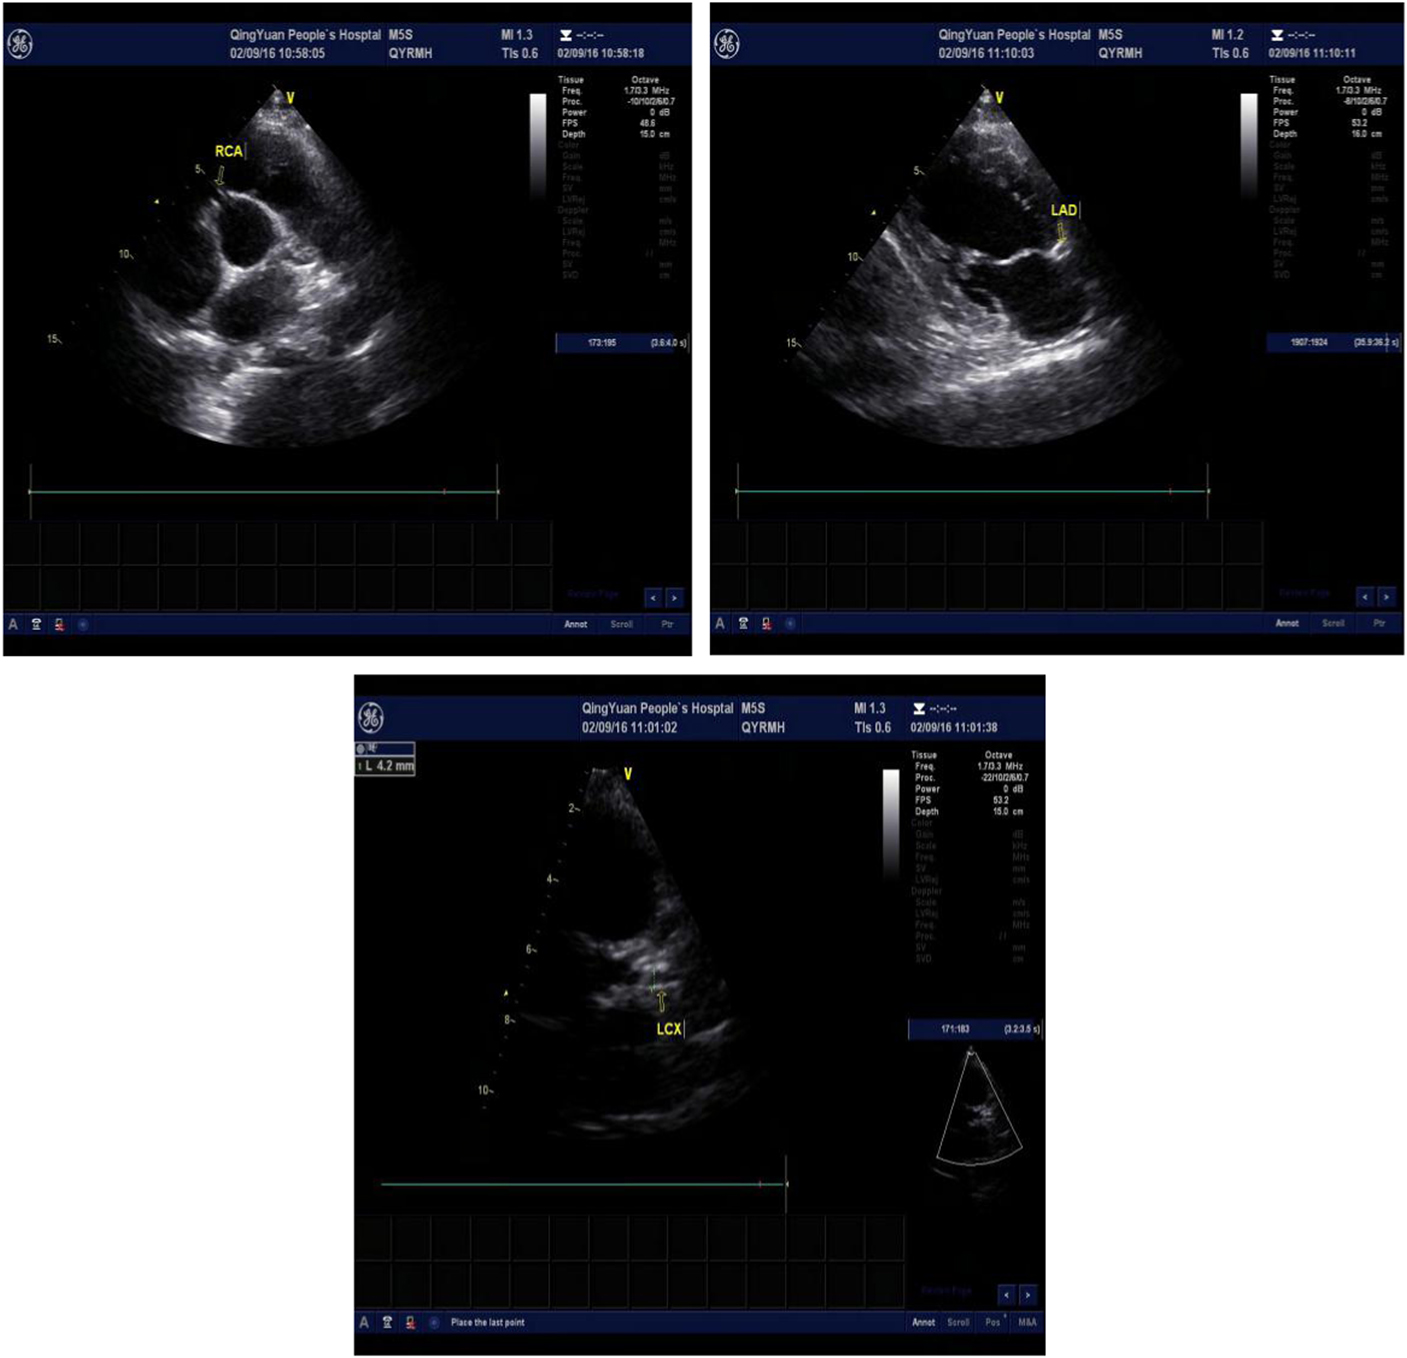

One day after the operation, his postoperative electrocardiogram showed that the elevated ST segments in II, III, aVF, and V4–V6 were down to baseline, and an inverted T wave began to appear in V2–V6 (Fig 4). An echocardiography performed 3 days after admission showed a left ventricular ejection fraction of 48.2%, enlarged bilateral atrium, dilated left ventricle, segmental weak pulse of left ventricular wall, mild regurgitation of bicuspid valve or of tricuspid valve, and the estranged left ventricular cells (Figs 5–7). Laboratory tests on the same day showed a higher troponin I of 31.833 ug/L, lower myoglobin of 27.9 ug/L, creatine kinase-MB of 21 U/L, creatine kinase of 74 U/L, and lactate dehydrogenase of 489 U/L. After 4 days, the serum laboratory results showed the following results: troponin I, 6.912 ug/L; myoglobin, 29.5 ug/L; creatine kinase-MB, 17 U/L; creatine kinase, 36 U/L; lactate dehydrogenase, 330 U/L; cholesterol, 2.86 mmol/L; low-density lipoprotein cholesterol, 1.63 mmol/L; triglyceride, 2.28 mmol/L; and high-density lipoprotein cholesterol, 0.57 mmol/L. All the related indexes were decreased. On the 14th day after the operation, the patient had a third examination of coronary arteriography, which revealed that there was barely any blockage caused by thrombi in the anterior descending branch and no stricture in the coronary artery (Figs 8 and 9). The patient was discharged on the 17th day, as his vitals were stable and symptoms disappeared.

Figures 5–7 Echocardiography shows the dilated left coronary artery and right coronary artery (RCA) (RCA 4.6 mm, left anterior descending artery (LAD) 6.6 mm, left circumflex artery (LCX) 4.2 mm).